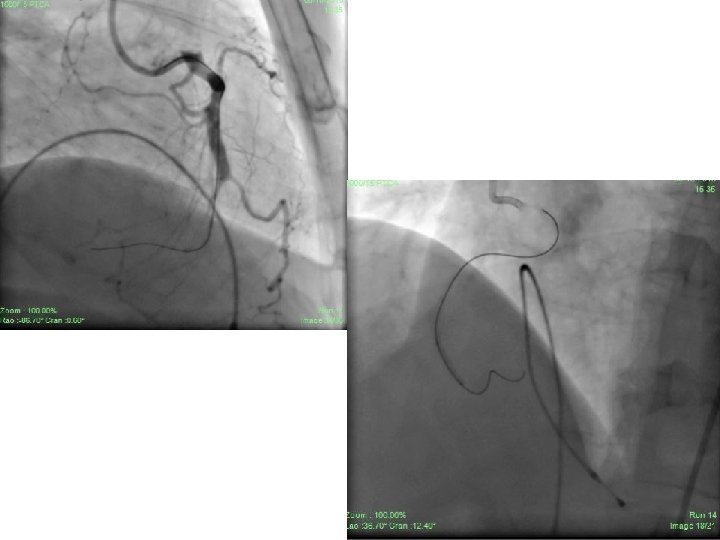

• Mr. LS, 50 yrs/Male, k/c/o HTN, CAD, AOE-II, DVD, smoker, dyslipidemic, non diabetic, no FHO CAD, presented with ACS/NSTEMI(Inferior wall MI) X 1 day duration with ongoing pain chest in spite of maximum anti anginal therapy. • BP 110/84 mm Hg. Pulse Rate 76/min. , regular, APPP • Blood biochemistry including lipid profile – WNL • Troponin I – Positive • Echo – RWMA in RCA territory with EF around 55%.

• CART done prior to ACS suggestive of DVD – Anomalous RCA from non-coronary sinus with oval orifice with acute angulation, proximal RCA – 40% stenosis and distal RCA – 99% stenosis with grade III inter coronary collaterals. • LAD having bifurcation lesion (1, 1, 1) with maximum 95% stenosis involving proximal, mid LAD and D 1. Distal LAD – 60% stenosis with grade I collaterals from RCA. • Right dominant circulation.

• Patient was taken up for PCI to RCA and LAD through RFA access under TPI. • RCA hooked initially with JR 3. 5/6 F guiding catheter then AL 1/6 F guiding catheter. • Lesion finally crossed with Miracle-3 wire using balloon support. • Lesion dilated with 1. 25 X 8 mm CTO balloon and 2. 0 X 15 mm Sprinter Legend balloon. • Xience-V 2. 75 X 28 mm stent deployed successfully in distal RCA with normal flow through and beyond stent. • TIMI – III flow achieved. • 50% residual stenosis remained distal to stent at crux and PLV.